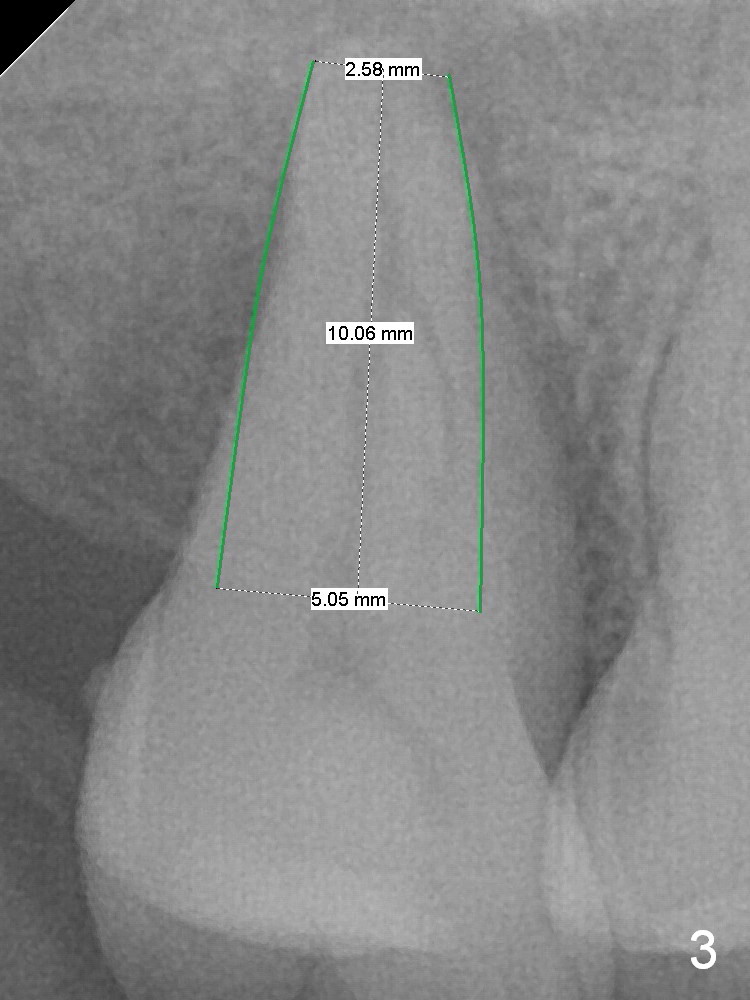

A 53-year-old man agrees implant treatment for crack tooth #2 (Fig.1). Since the apex overlaps the sinus floor (Fig.2 panoramic X-ray), the primary stability will be derived from tight contact of an implant with the socket. After extraction (Metronidazole), osteotomes are going to be used to break through the sinus floor (RT2-4), followed by tap drills (4.5 mm or larger (Fig.3) until achieving 35 Ncm). The implant will be one size larger. Prepare regular and extra wide surgical kits. Before implant placement, insert PRF plug and allograft/Osteogen.